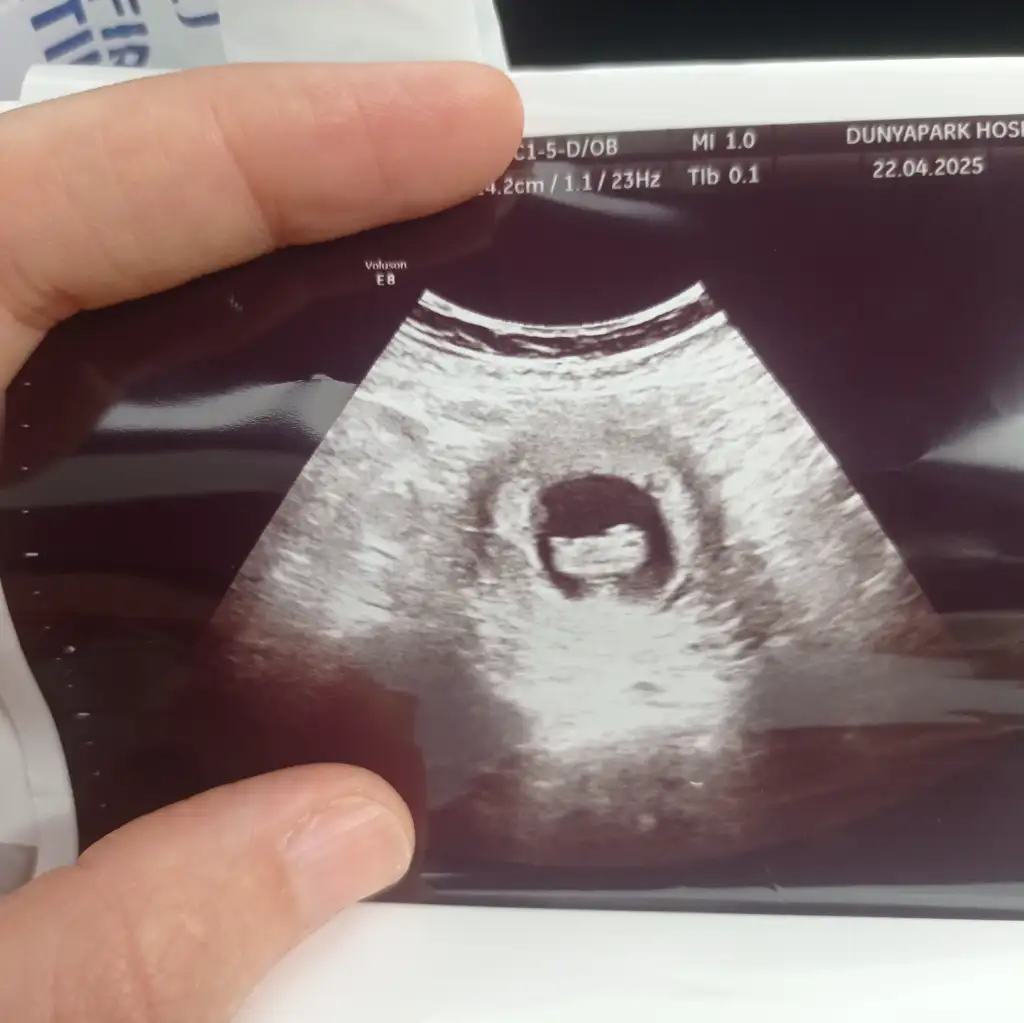

Yazmayı unuttum 6 haftalık karından bakıldıMerhaba benim bebeğime de bakabilir misiniz

Ay çok merak ediyorum bizede bakar mısınız karından ultrason ile bakıldı görsellerde ilk görsel 10+4 diğer görseller 6+4 haftalıkken bir oğlum var bide kızımız olur inşallah :)Kızlar 6-8 haftalık ultrason görüntülerinizi atın tahmin yapalım . Ya da cinsiyeti öğrenen annelerimiz 6-8 haftalık görüntülerini atsın bize de fikir olsun

Yok karindan ultrasonBir oğlum var kızım olmasını da isterimsizinde Vajinal ultrason görüntüsümüydü

Kız bebek gibiBenimde 8+2 haftalık bakar mısınız acaba cinsiyeti ne ?